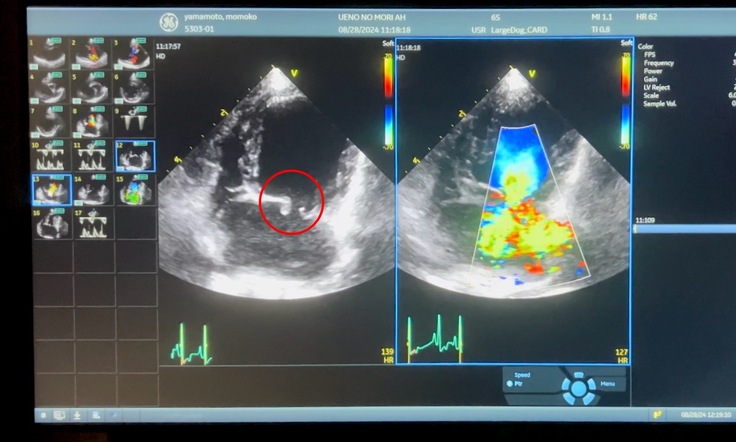

次は"僧帽弁"の画像です。

・昨日のももの僧帽弁です

左の赤丸の部分が"弁"です。正常な心臓はこれがパタパタと開閉しながら血液を送ります。しかし弁がもろくなったりしきちんと閉じなくなると、その隙間から右のように血液が逆流していきます。

この逆流した血液の量が増えると、行き場を失い肺に流れます。肺に流れた血液も増え過ぎると血液中の水分が肺に溢れ出します。その状態がいわゆる肺水腫です。